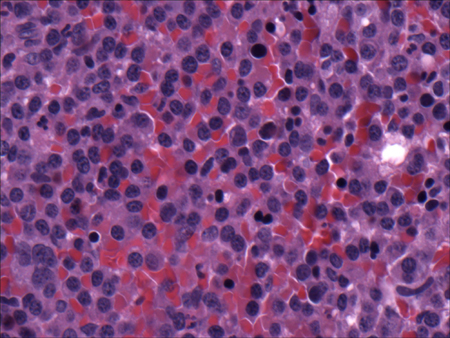

- renal biopsy:

interstitial inflammation with eosinophils